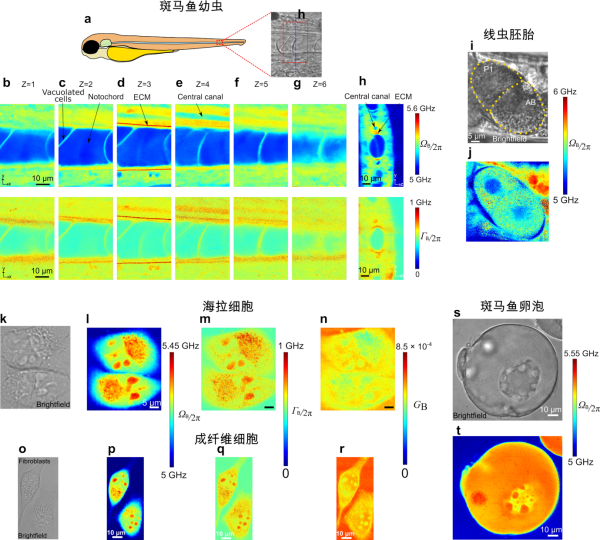

新成像技术能同步观测细胞精细结构